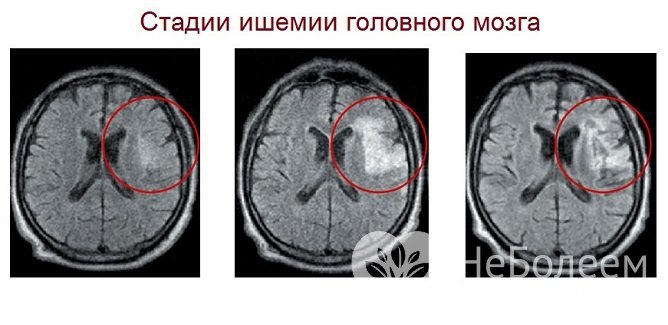

Источник: golovnayabol.comТечение ишемии головного мозга подразделяется на несколько стадий: